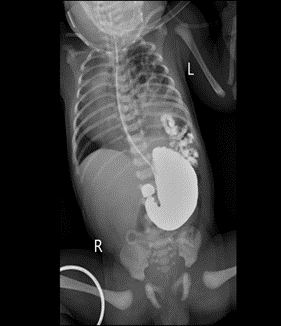

随着医学的进步,产检的普及,很多新生儿的先天性畸形都能在胎儿期的时候发现。先天性膈疝就是其中的一种。因为这个疾病的发生率比较低,一般为1/4000-1/3000,大家对它很陌生,所以在产检发现这个问题的时候就难免特别紧张和焦虑。这次,我们就来说说先天性膈疝,看看它究竟是何方神圣。

膈疝会有什么危害呢?最大的危害就是会影响肺的发育,影响肺的工作。一般的情况下,腹腔压力要比胸腔大,所以膈疝形成后绝大多数情况都是腹腔脏器通过膈肌的缺损进入胸腔。作为肺,本来有个“房子”(胸腔)可以好好的成长、好好的工作,结果这个“房子”质量不好,管不住门,结果被腹腔里的肠管、脾脏的霸占了一部分,肺生存空间小了,自然发育不好功能不好,将来出生以后会出现支气管肺发育不良,有的可能出现呼吸衰竭的情况。其次,腹腔内的肠管、脾脏、肝脏等因为霸占了肺的地盘,觉得自己无忧无虑了,也就放飞自我了,肠管不按照正常的程序旋转,肝脾也没有韧带约束,于是可能出现游走的脾脏、先天性肠旋转不良等等畸形,可能影响胃肠道功能。

说了这么多,膈疝应该怎么治疗呢?方法只有一个——手术修补缺损,让腹腔和胸腔完全分开,泾渭分明,井水不犯河水,把空间还给肺,让它有机会能好好生长,好好工作。目前膈疝的主流手术方法是从胸腔内修补膈肌缺损,很多情况下可以做微创手术。修补的时候绝大多数可以直接使用已有的膈肌组织用针线缝合修补。但对于缺损较大的膈疝可能需要使用补片,就像女娲补天需要用五彩石一样。那手术风险大吗?其实新生儿做手术风险都有些大的。一般的同样的手术,和婴儿相比,新生儿手术的风险很大一部分来自麻醉。新生儿对买醉药代谢慢,买药作用容易蓄积,为了维持麻醉状态一般都会根据手术时间调整麻醉药的用量。其次,新生儿的体表面积体积比较大,在手术中容易丢失热量导致体温下降。因此可以看出,手术时间越长,风险是越大的。传统的膈疝修补需要一针一针的缝合,一般时长需要近2小时。而目前我们治疗先天性膈疝采用新型的微创手术,胸腔镜下修补膈疝,用编织线结扎修补膈肌的缺损,就像扎麻袋口一样,手术时间可缩短至20分钟左右,可以大大降低手术麻醉带来的风险,对组织的创伤小,对肺影响小,手术切口基本可达到无痕的水平,大大加快了膈疝术后的恢复。